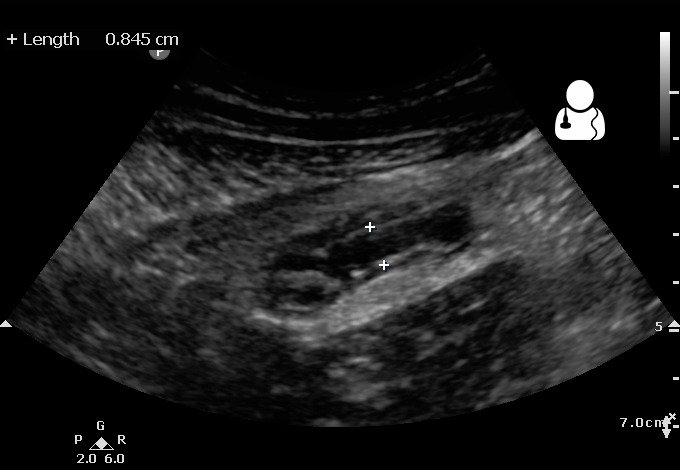

Of course, it happens. Patients with suspected pneumonia or suspected fractures may require X-ray or CT. In this case, the abdomen in which the fetus is located is covered with a shield which prevents the radiation. Especially for non-abdominal examinations, the radiation exposure of the fetus is insignificant. If the stomach is sore and needs inspection, we use ultrasound or MRI without radiation. If you tell that you are pregnant, the inspection is always carried out in consideration of radiation.

Acute appendicitis diagnosis by ultrarsound

From: https://www.ultrasoundoftheweek.com/uotw-45/